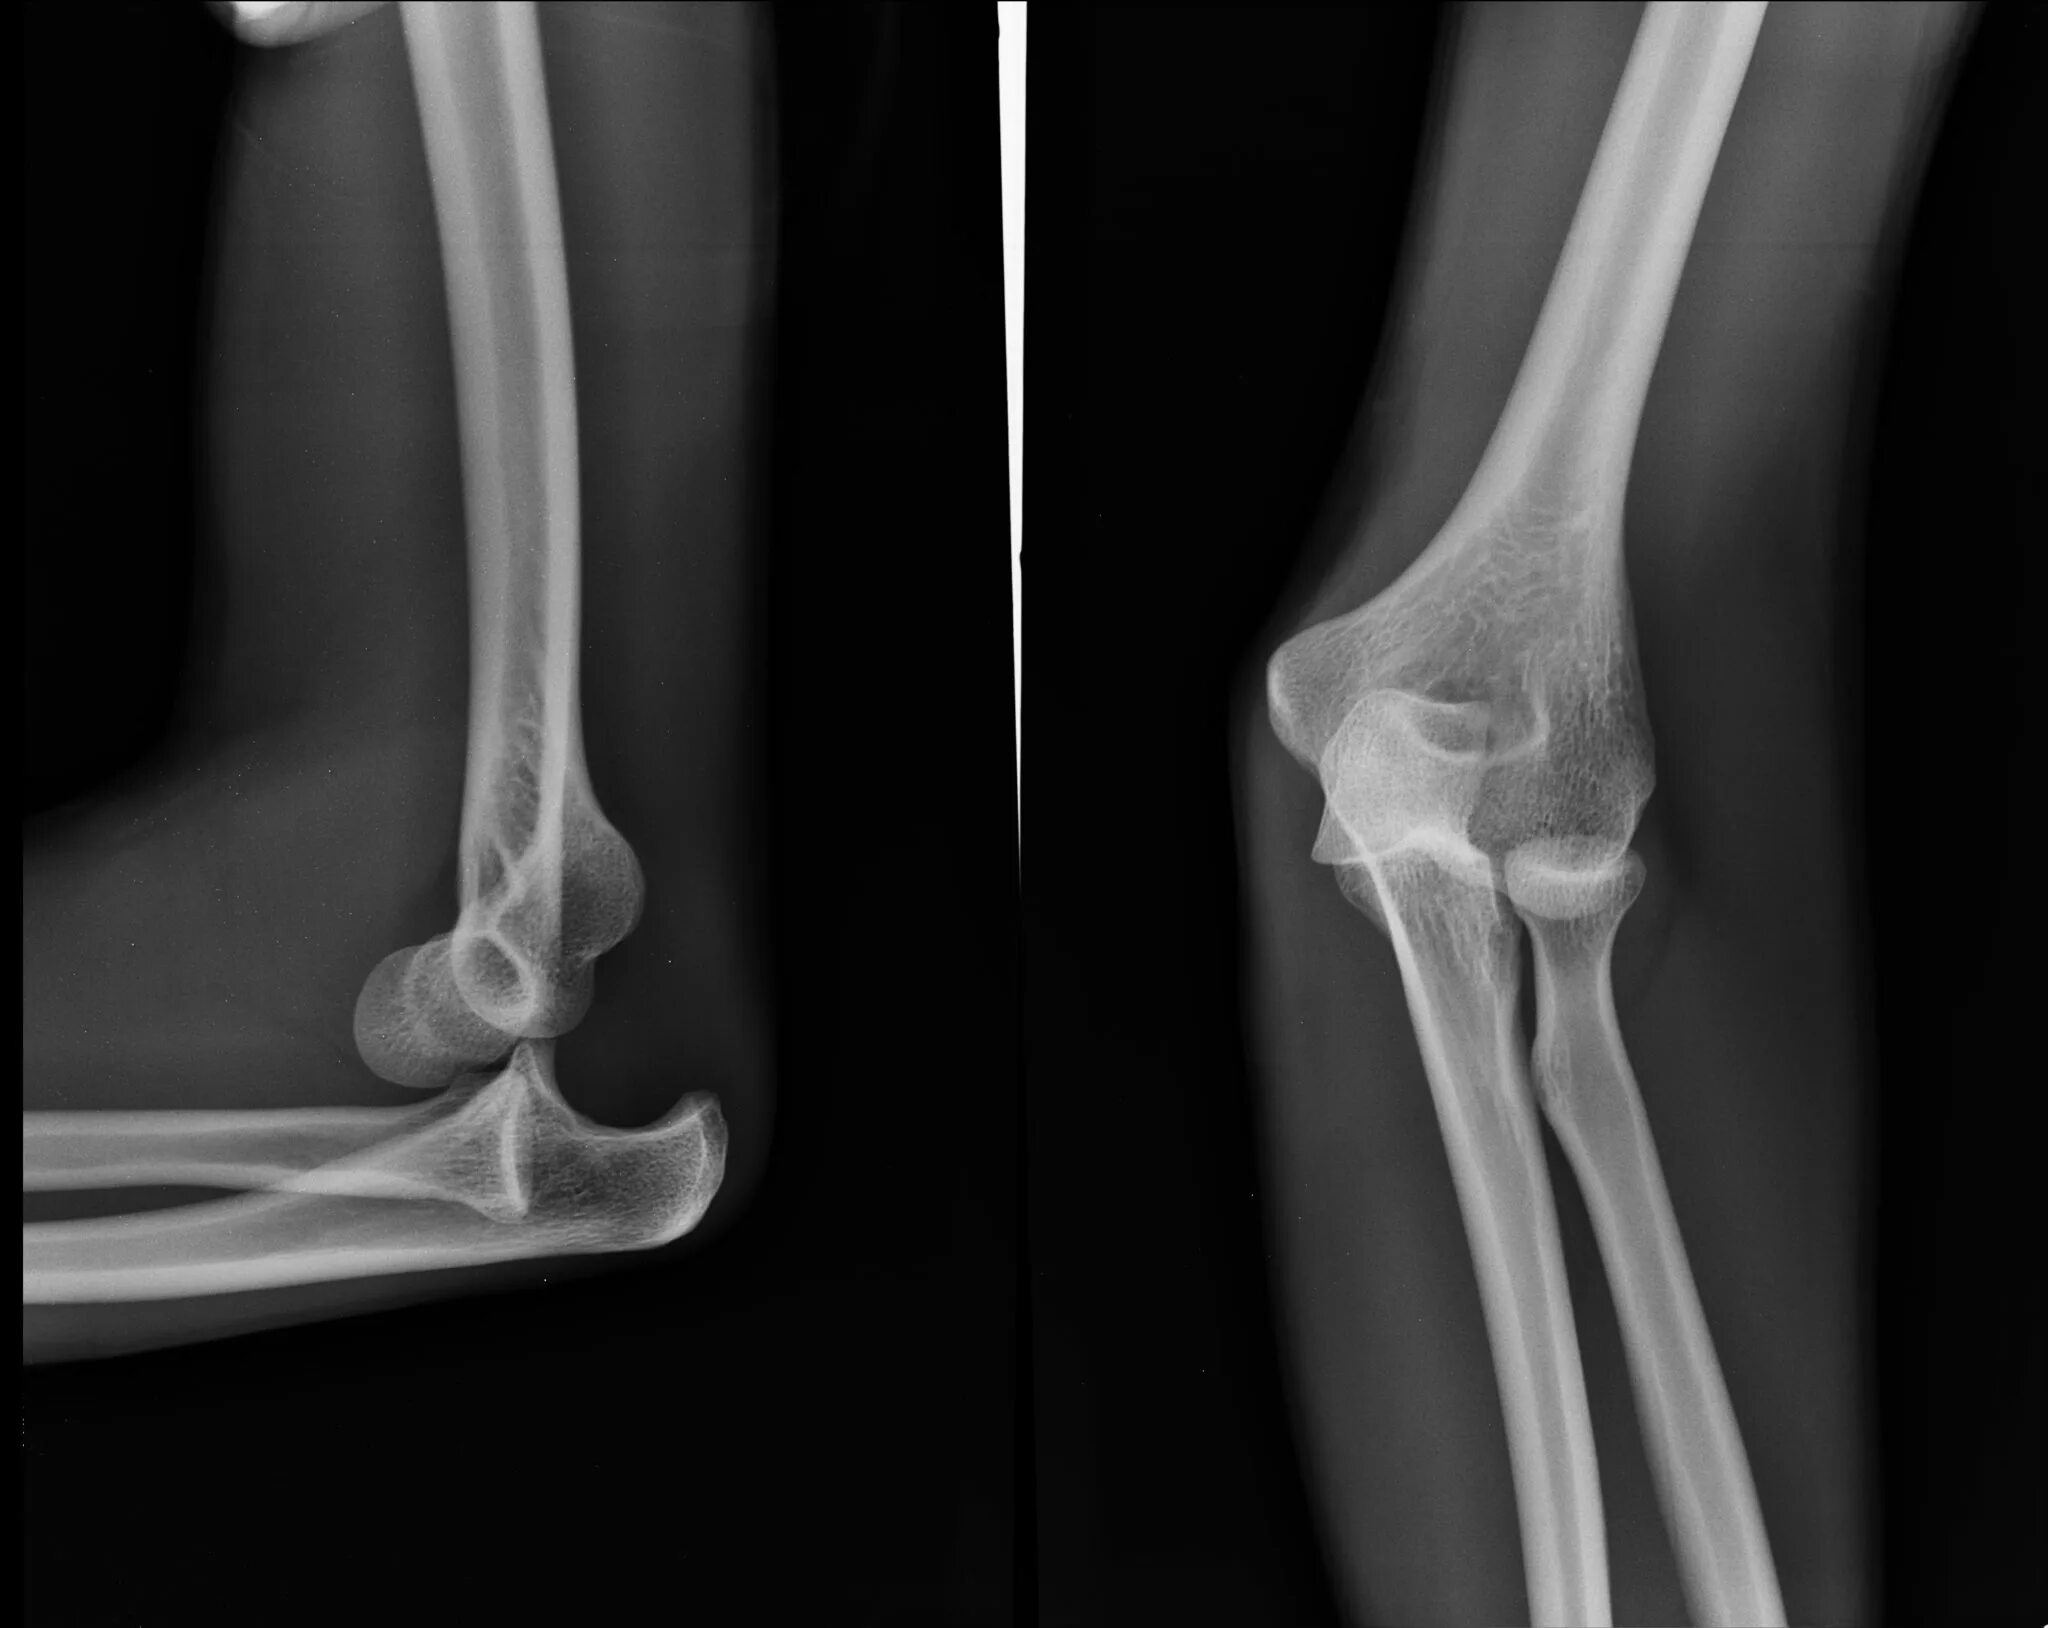

Подвывих локтевого сустава у ребенка